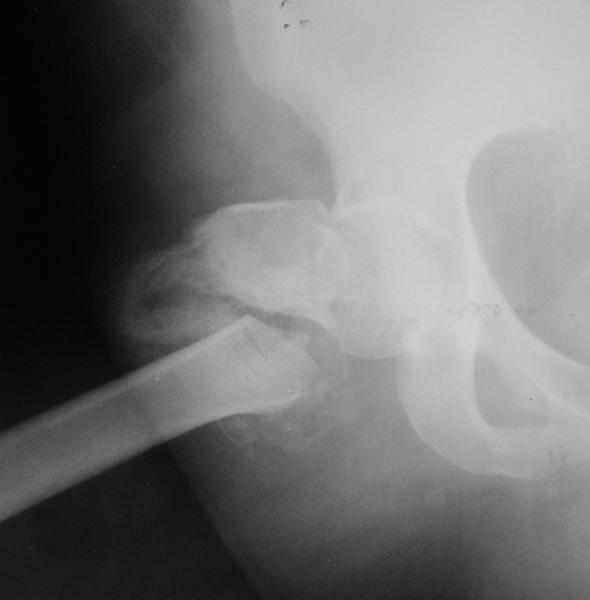

Уважаемые коллеги, хотелось бы услышать ваше мнение по следующему случаю: Относительно молодая женщина(39 лет), поступила в клинику в марте 2005 года, через 3 месяца после травмы с Неправильно срастающимся поперечным межвертельным переломом правого бедра. Был выполнен закрытый интрамедуллярный остеосинтез правого бедра канальным реконструкционным стержнем ChM. Ожидали бОльших проблем на операции, результату обрадовались. Как оказалось, зря. Сращение наступило через 3,5 месяца после операции. В ноябре 2005 года произошел перелом шейки бедра и винтов в ней. В апреле 2006 импланты были удалены. В приложении фото и рентгенограммы больной. Сопутствует ожирение 4 ст. (при росте 168 см., вес больной 140кг.), сахарный диабет II тип. Имеется медиальная неустойчивость коленного и голеностопного суставов, при нагрузке колено вальгируется на 15-20 градусов. Вопросы: 1.Целесообразность эндопротезирования (в настоящий момент передвигается на ходунках)? 2.Если ответ на первый вопрос-да, то каким протезом? 3. С какими проблемами можем столкнуться во время и после операции? Заранее благодарен за ответы. Салават Салаватов, Екатеринбург